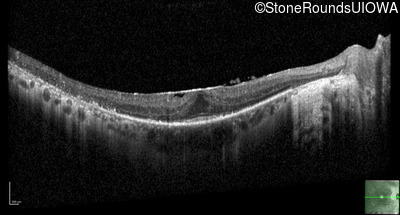

Optical Coherence Tomography - Right - 20/20

Exemplar / OCT Stack

OCT Stack